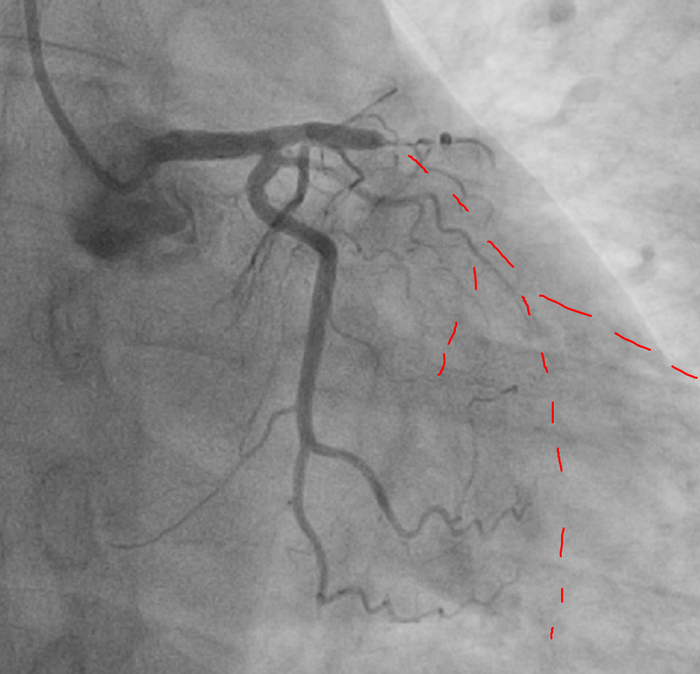

Далее левая коронарная артерия:

Принимаю решение "исправлять" все сразу